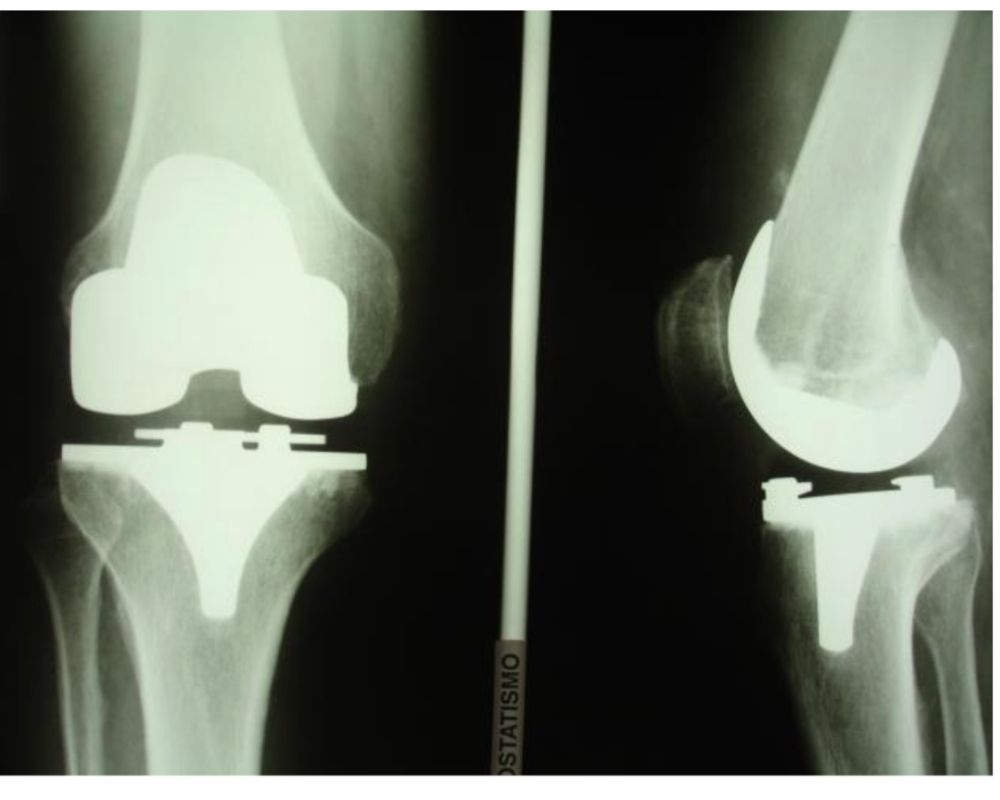

Rx postoperatoria

Protesi totale

Protesi totale di ginocchio

L’articolazione del ginocchio è costituita dalla parte distale del femore, dalla parte prossimale della tibia e dalla rotula. L’intervento di protesi al ginocchio prevede la sostituzione delle superfici articolari danneggiate.

In particolare, la protesi di ginocchio è composta da:

• una componente femorale, fissata sulla superficie distale del femore perfettamente sagomata;

• una componente tibiale, fissata sulla parte superiore della tibia, che viene resecata in modo tale da correggere eventuali difetti di allineamento del ginocchio (varo-valgo);

• un inserto in polietilene che, inserito sulla componente tibiale, svolge un’azione ammortizzante tra la componente femorale e quella tibiale.

Talvolta si usa una componente rotulea in polietilene, applicata sulla superficie articolare della rotula opportunamente resecata; tuttavia oggi le componenti femorali delle protesi moderne consentono di non protesizzare la rotula.